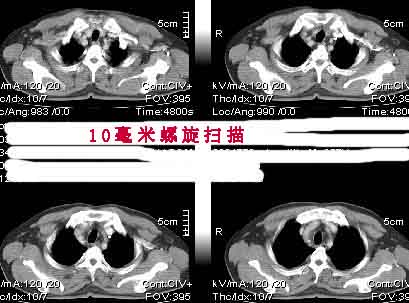

该病例我的诊断意见:右肺上叶周围型肺癌伴纵隔和右肺门淋巴结增大和右肺上叶阻塞性肺炎{病灶周围致密影以近肺门侧明显!}。右侧少量胸腔积液。

一. 1)症状有无发热及慢性过程.2)化验室检查?3)有无tb接触史?二.右肺上叶见片团状影,边界欠清,外侧方见一结节状软组织影,密度欠均匀,内可见低密度坏死区.周围强化明显,肺内见纤维索条影,局部胸膜增厚,但无明确胸膜凹陷.上叶支气管壁增厚,肺门及纵隔淋巴结增大.右侧胸腔少量积液.诊断意见:1右肺上叶慢性感染性疾病(肺tb?)伴肺门,纵隔淋巴结大.右胸少量积液.右肺上叶结节影多为tb球?2右肺上叶周围型肺ca伴肺门,纵隔淋巴结转移待排.右肺上叶炎变(肺门及纵隔淋巴结压迫).右胸少量积液.等待随返结果.